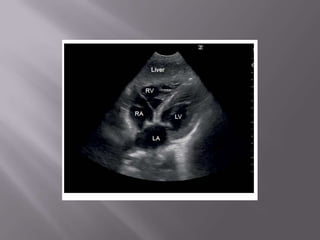

Ferramenta não apenas diagnóstica como de monitorização  Fundamental na abordagem do choque e da dispnéia  Permite em segundos descartar embolia pulmonar e tamponamento cardíaco como causas do choque  Usado na PCR – determinar causa reverível – durante a checagem do Pulso!  Transtorácico ou Transesofágico?